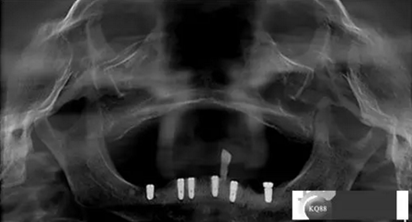

3,治療計(jì)劃:依據(jù)檢查及主訴,擬323436434446植入6顆osstem植體,無(wú)即刻拔除33殘冠目的方便戴過(guò)渡性臨時(shí)活動(dòng)義齒,6個(gè)月后完成二氧化鋯冠橋修復(fù)

2)術(shù)前準(zhǔn)備及手術(shù)過(guò)程,測(cè)量血壓及血糖,簽種植知情同意書(shū);嚴(yán)格遵循無(wú)菌操作,局麻下采用微創(chuàng)技術(shù)于323436分別植入osstem4.0X10,4.0X10,4.5X7; 434446分別植入osstem4.0X1O,4.0X10,4.5X7.初期穩(wěn)定性均達(dá)到了35N.CM以上;嚴(yán)密縫合,止血,種植體位點(diǎn)和方向與設(shè)計(jì)一致。

戴牙:試戴,拍片確定邊緣密合后調(diào)整咬合,試戴一周后患者適應(yīng),咬合良好,基臺(tái)加力30N.CM,粘接劑粘固,去除多余粘結(jié)劑,拍片確定有無(wú)粘接劑殘留,并進(jìn)一步微調(diào)咬合